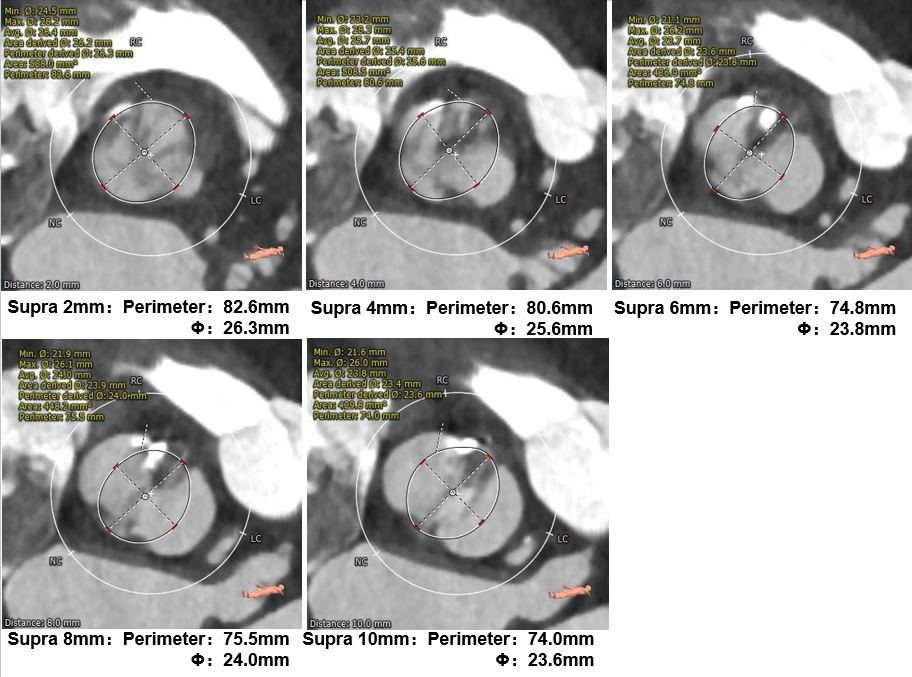

主动脉根部测量

瓣上测量

患者男,65岁,重度主动脉瓣狭窄诊断明确,符合TAVR手术适应症。通过对CT数据进行分析提示Type0型二叶式主动脉瓣,瓣叶钙化较轻且仅位于右冠窦,瓣膜锚定存在一定困难;经多平面测量分析,瓣环周长径约27mm,瓣上限制较大,左室心肌显著增厚,心腔偏小,存在循环崩溃风险。经王焱教授、王斌教授及吉林大学中日联谊医院TAVR团队对该病例进行全面讨论后,制定22mm球囊预扩,预装AV26瓣膜的手术策略;术中在瓣膜完全释放后出现血压下降,TAVR团队沉稳处理,排除心包积液、主动脉瓣大量反流等因素后,给予0.9%NaCl静脉推注+静脉滴注、多巴胺静脉泵入等对症治疗后血压逐渐恢复并持续稳定,术后超声评估各项参数满意,效果显著,为患者带来极大获益。